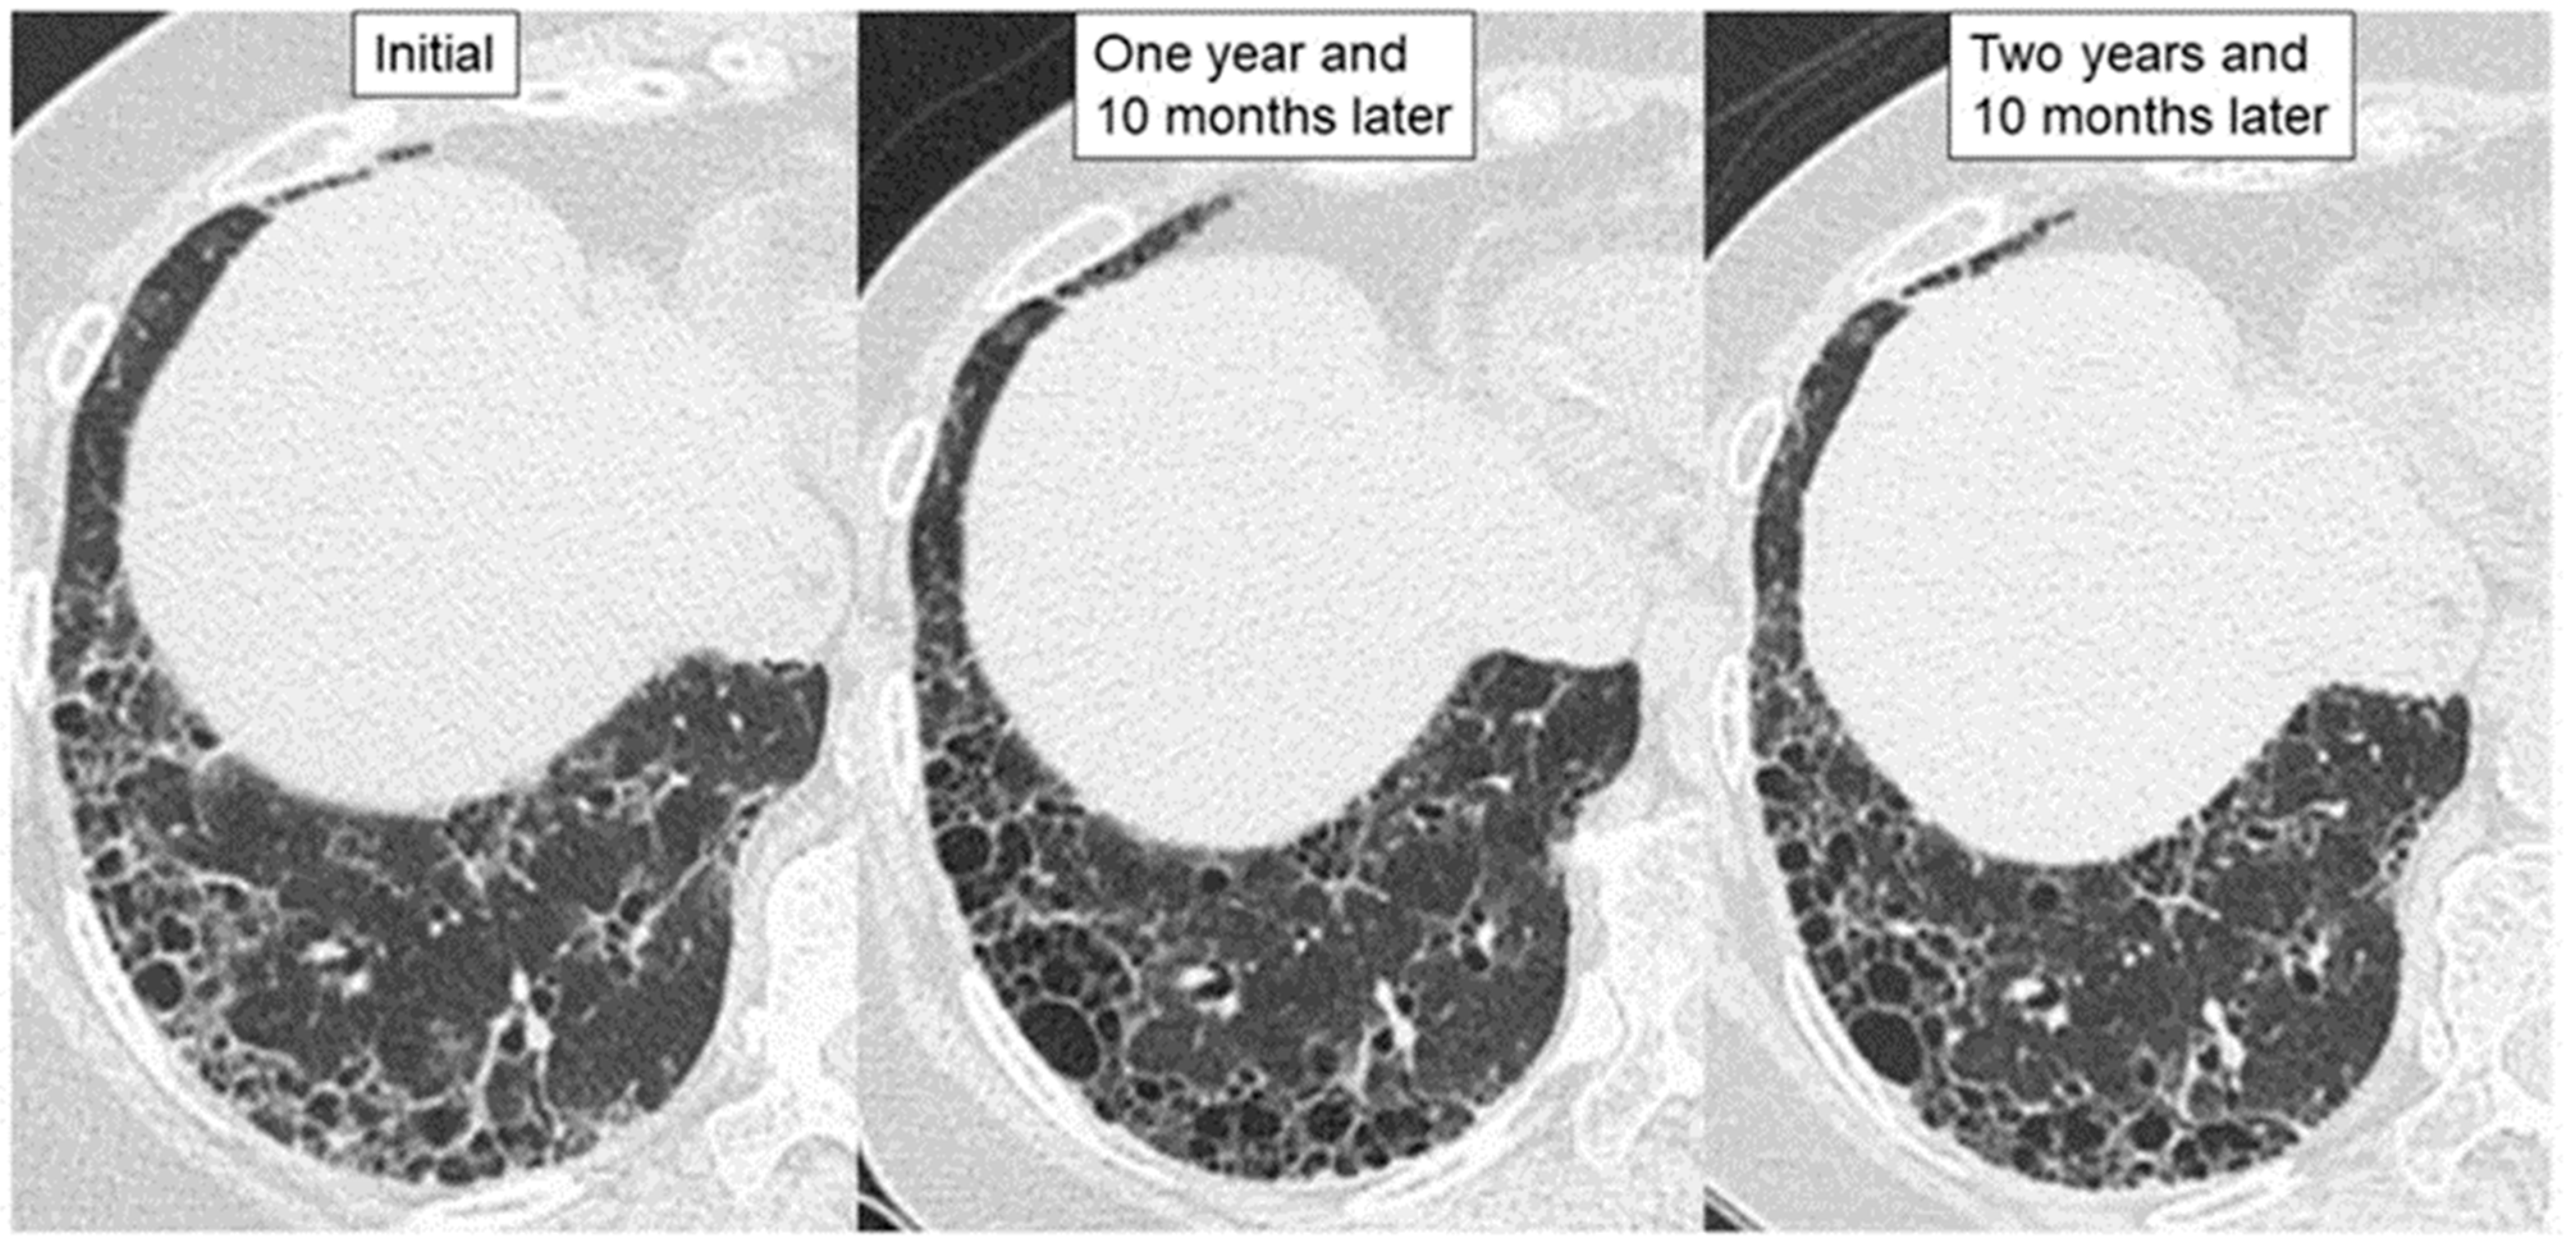

| HRCT findings | Framework: Subpleural and basal predominant distribution is often heterogeneous | |

| Increased attenuation around honeycombing and traction bronchiectasis (19–39%) | ― | |